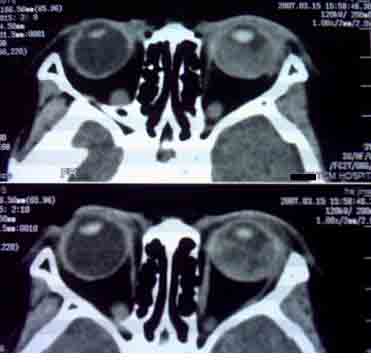

患者,偶然发现左眼无光感,平时,无明显不适,眼外观无明显异常。

首先考虑视网膜母细胞瘤。

支持左侧视网膜母细胞瘤,可惜没有钙化。

大家有没有想到有哪些需同成视网膜细胞瘤鉴别诊断的疾病?正是没有钙化,所以此病首先更应该考虑什么?请大家说说看。

考虑左侧眼球渗出增殖性视网膜炎所致视网膜剥离,建议mri检查。

1.ct表现:眼球内均匀高密度肿块,有增强,并多有点状或团块状钙化,在3岁以下的儿童有极大的诊断价值。可见相关视网膜下积液。

2.mr表现:肿瘤t1加权像为较视网膜略高或与视网膜相等的信号强度,t2加权像为低信号强度。大钙斑t1、t2加权像均为低信号斑,小钙斑不易显示。视网膜下积液或积血显示清楚。

鉴别诊断 :需与渗出性视网膜病鉴别。